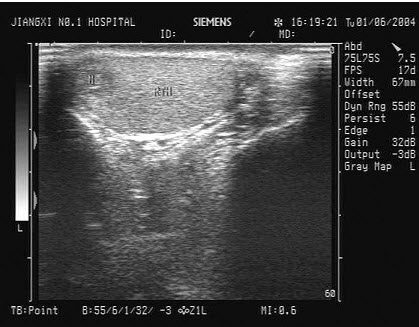

4、单项选择题

女性,于膀胱输尿管位置见一囊性光团,有规律收缩,增大。如图所示,考虑为()

A.膀胱肿瘤

B.膀胱憩室

C.输尿管结石

D.输尿管囊肿

E.膀胱异物